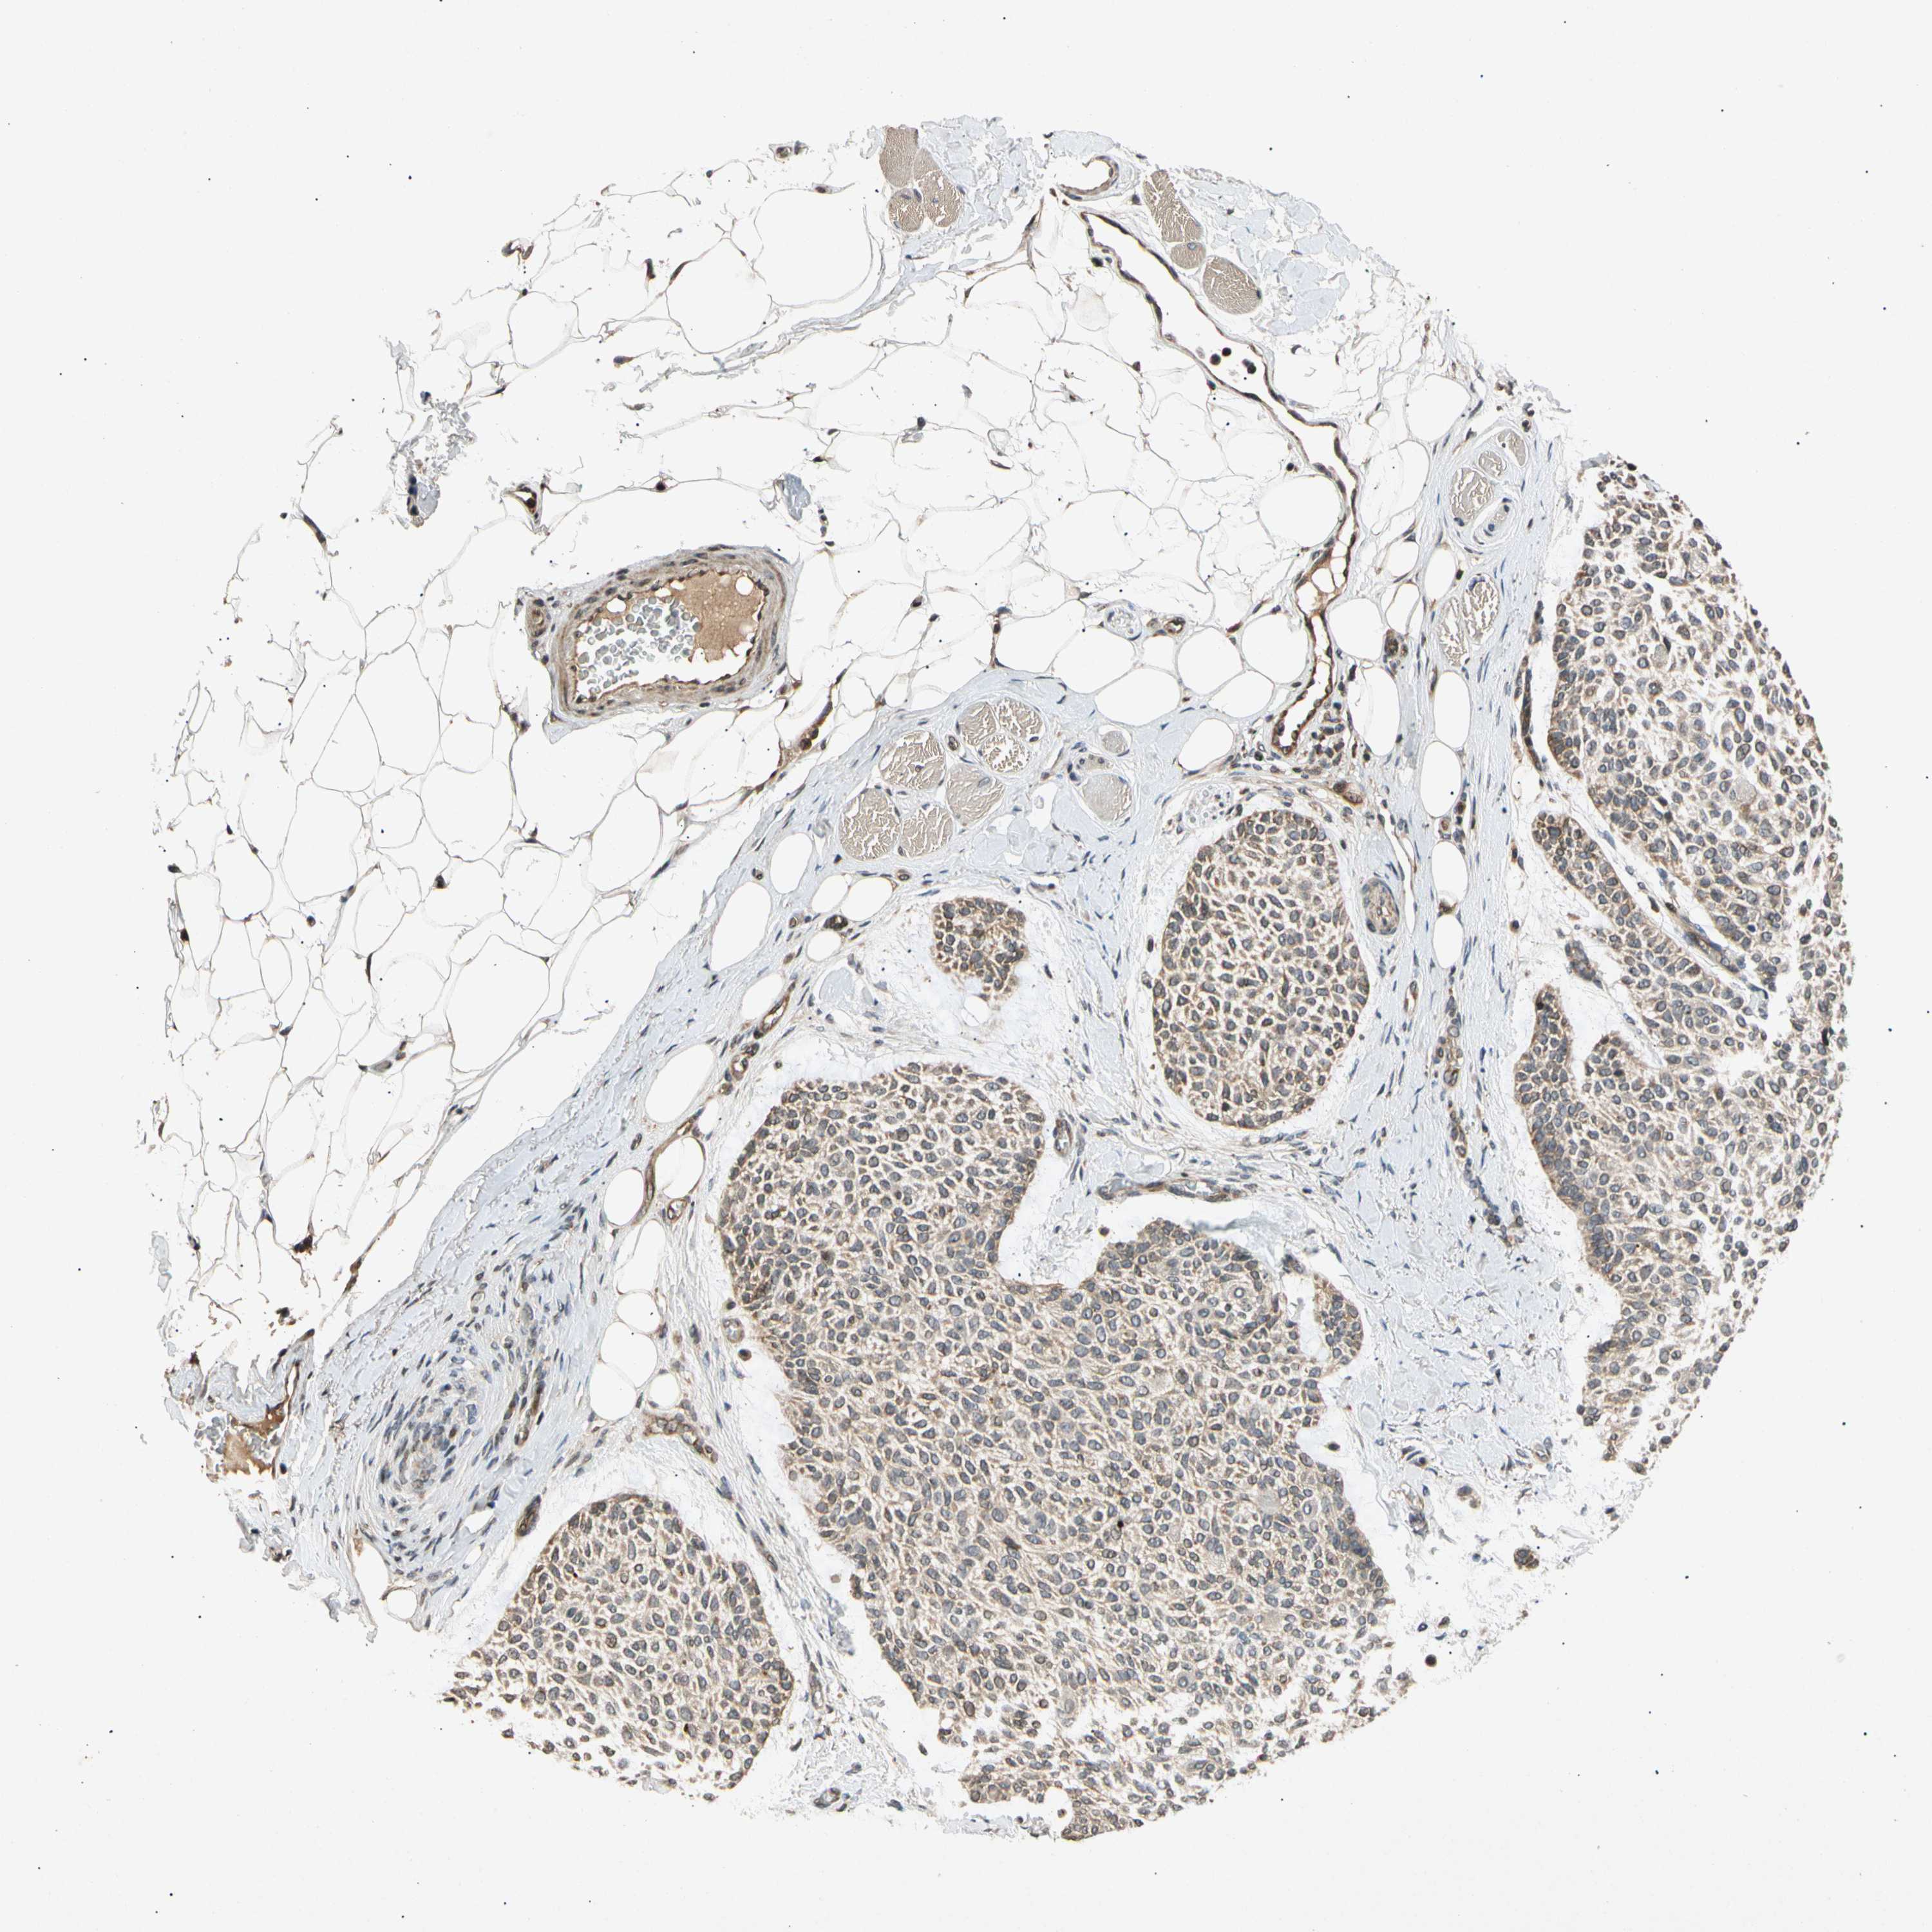

CANCER SKIN CANCER Show tissue menu

Basal cell and squamous cell cancer

SKIN CANCER - Protein expressioni

A mouse-over function shows sample information and annotation data. Click on an image to view it in a full screen mode. Samples can be filtered based on level of antibody staining by selecting one or several of the following categories: high, medium, low and not detected. The assay and annotation is described here.

Each image is clickable and will lead to virtual microscopy that enables deeper exploration of all samples and also displays staining intensity scores, fraction scores and subcellular localization as well as patient and tissue information for each sample.

Antibody HPA006083

Squamous cell carcinoma, NOS

Basal cell carcinoma